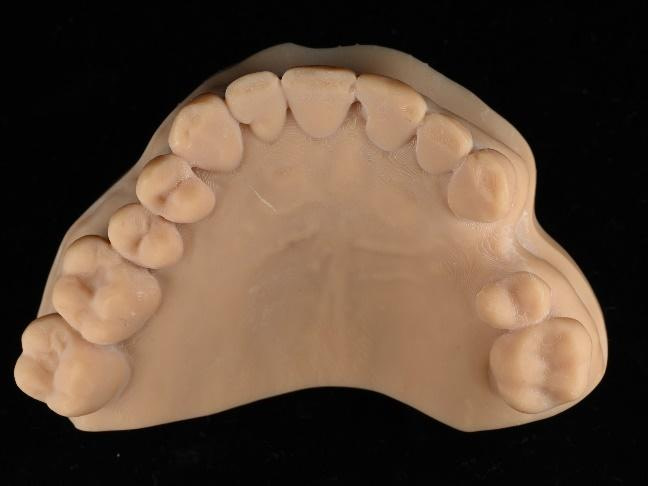

The crown was milled from a high-strength, multilayered zirconia and hand-finished to achieve a lifelike appearance.

At the final appointment, the crown was securely attached to the implant, resulting in a beautiful, natural-looking restoration.